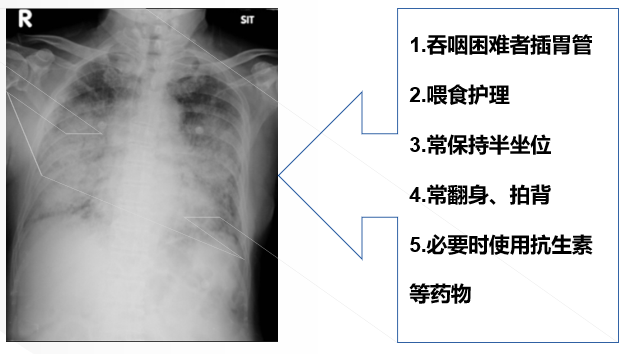

①肺炎